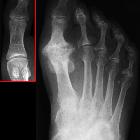

Hallux

großer Zeh

Hallux valgus

Hallux rigidus